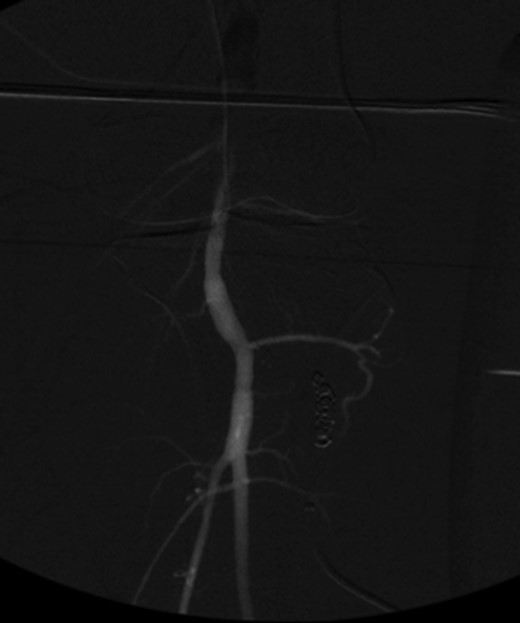

Patient underwent a left lower extremity angiogram. During the procedure she was found to have patent aorta and bilateral common iliac artery. There was no disease visualized in the left external iliac artery, common femoral artery (CFA), SFA, patent previously placed stent, patent above and below the knee PA and two vessel run off to the foot (Fig. 1). Upon delayed fluoroscopic images we identified contrast filling the deep venous system rather quickly suggesting a high volume fistula (Fig. 2). We then identified the fistula between ATA and ATV. Although ATA was previously ligated there was retrograde filling of the artery from unnamed branches, which communicated with the venous system as shown in. In the midcalf (ATA) was cannulated with a micropuncture needle. Micropuncture wire was inserted and a 5-Fr sheath was inserted after exchanging over wire. At this point VortX coils (Boston Scientific) were placed from the curve of ATA until the whole AVF was sealed. Anterograde angiogram showed no flow through the fistula (Figs 3 and 4). There was a palpable PT and DP pulse at the completion of the procedure. Sheath was removed, pressure dressing applied. Patient was discharged home same day. Recovery has been unremarkable. Three months follow-up claudication symptoms have significantly improved.

Fluoroscopy showing; left external iliac artery (EIA), common femoral artery (CFA), superficial femoral artery (SFA), patent previously placed stent, patent above and below the knee popliteal artery (PA) and two vessel run off to the foot.